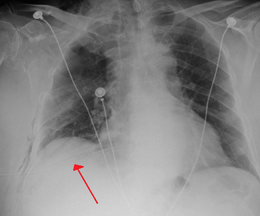

A large right-sided spontaneous pneumothorax (left in the image). An arrow indicates the edge of the collapsed lung | |